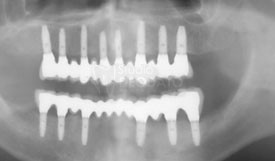

Rx-OPT di controllo subito dopo il posizionamento implantare e protesico.